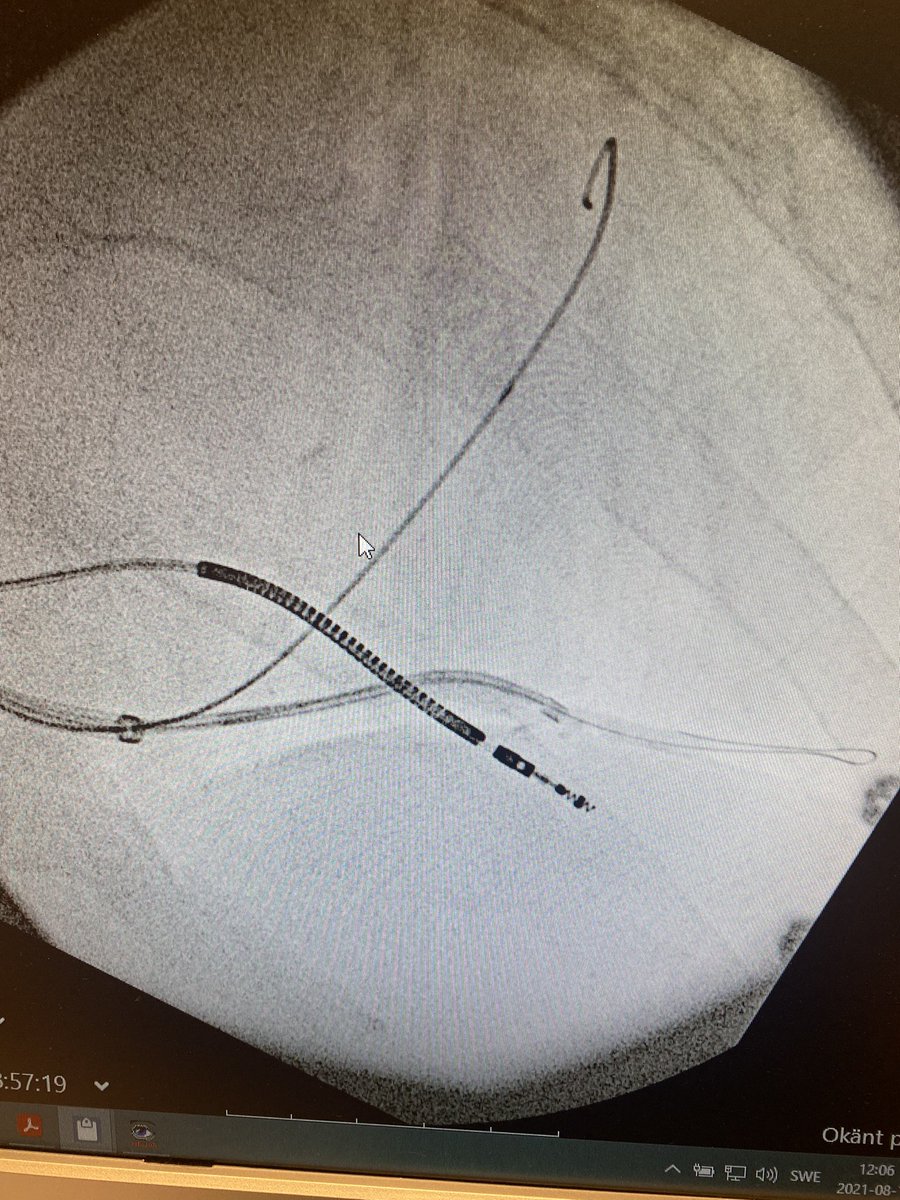

Images from the previous case

Right sided CRT upgrade in patient with laminopathy and huge (10x10cm) right atrium. Easy CS cannulation with Worley sheath + handshaped Cordis MPB 1 guide and then amplatz wire for stability during PL lead placement - thank you @seth_j_worley for tips!